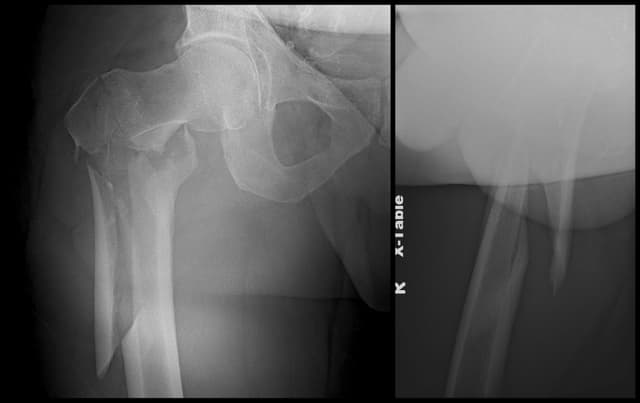

Subtrochanteric Femur ORIF

Pre-op